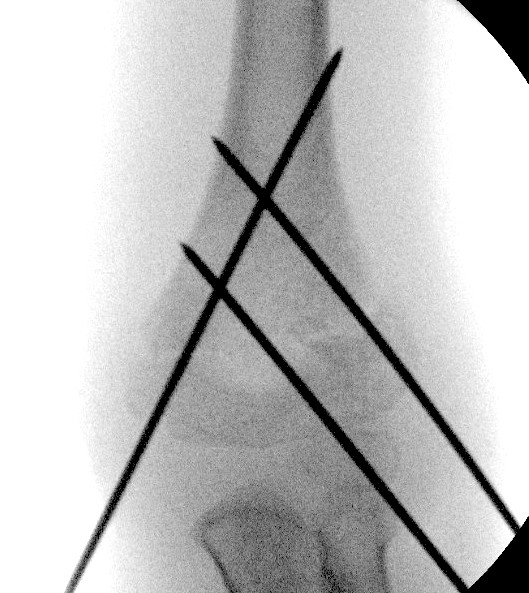

4. Flexion pushing olecranon forward with thumb

- shoot through AP to assess reduction

- check Baumann's angle

- check medial and lateral columns with oblique views

6. Check lateral image

- lock elbow in flexion and rotation

- externally rotate the shoulder

- ensure that the anterior humeral line is correct

- reduction of teardrop on lateral

- may need to increase the flexion

2 x lateral K wires

Technique

- hold elbow in flexion

- place K wire into lateral condyle

- place other index finger on the humerus to guide aim

- 2 x lateral 1.6 mm K wires (consider 2 mm K wires in larger children)

- one K wire on the direct lateral surface, just lateral to the capitellum

- one on the capitellar surface

Points

- must engage medial and lateral columns (bicortical)

- make pins divergent for increased stability

- only need 3rd pin if first two not divergent enough

Check stability

- place elbow into extension